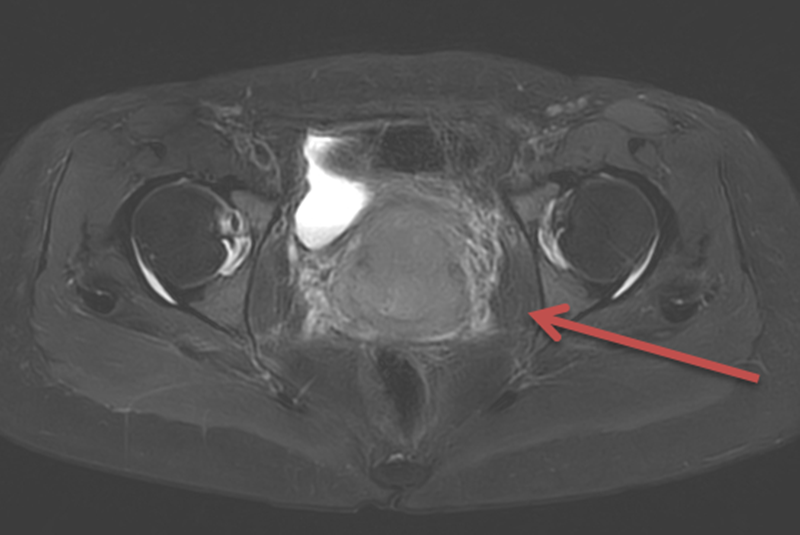

MRI检查:宫颈明显增大,呈软组织肿块影,T1W1呈低信号,T2W1-FS呈稍高信号,DW1序列呈高信号,ADC图呈低信号,增强后不均匀强化,601/IM6示较大截面范围约7.43*5.42cm,符合宫颈癌征象,病灶向上累及宫体下段,向下累及阴道上中段及穹隆,膀胱后壁、直肠前壁、两侧宫旁拟受侵犯可能,两侧盆壁、髂血管旁多发肿大淋巴结;右侧耻骨转移。盆腔内少量积液,右侧附件暂拟生理性改变。

10

图4. MRI结果提示宫颈明显增大,符合宫颈癌征象